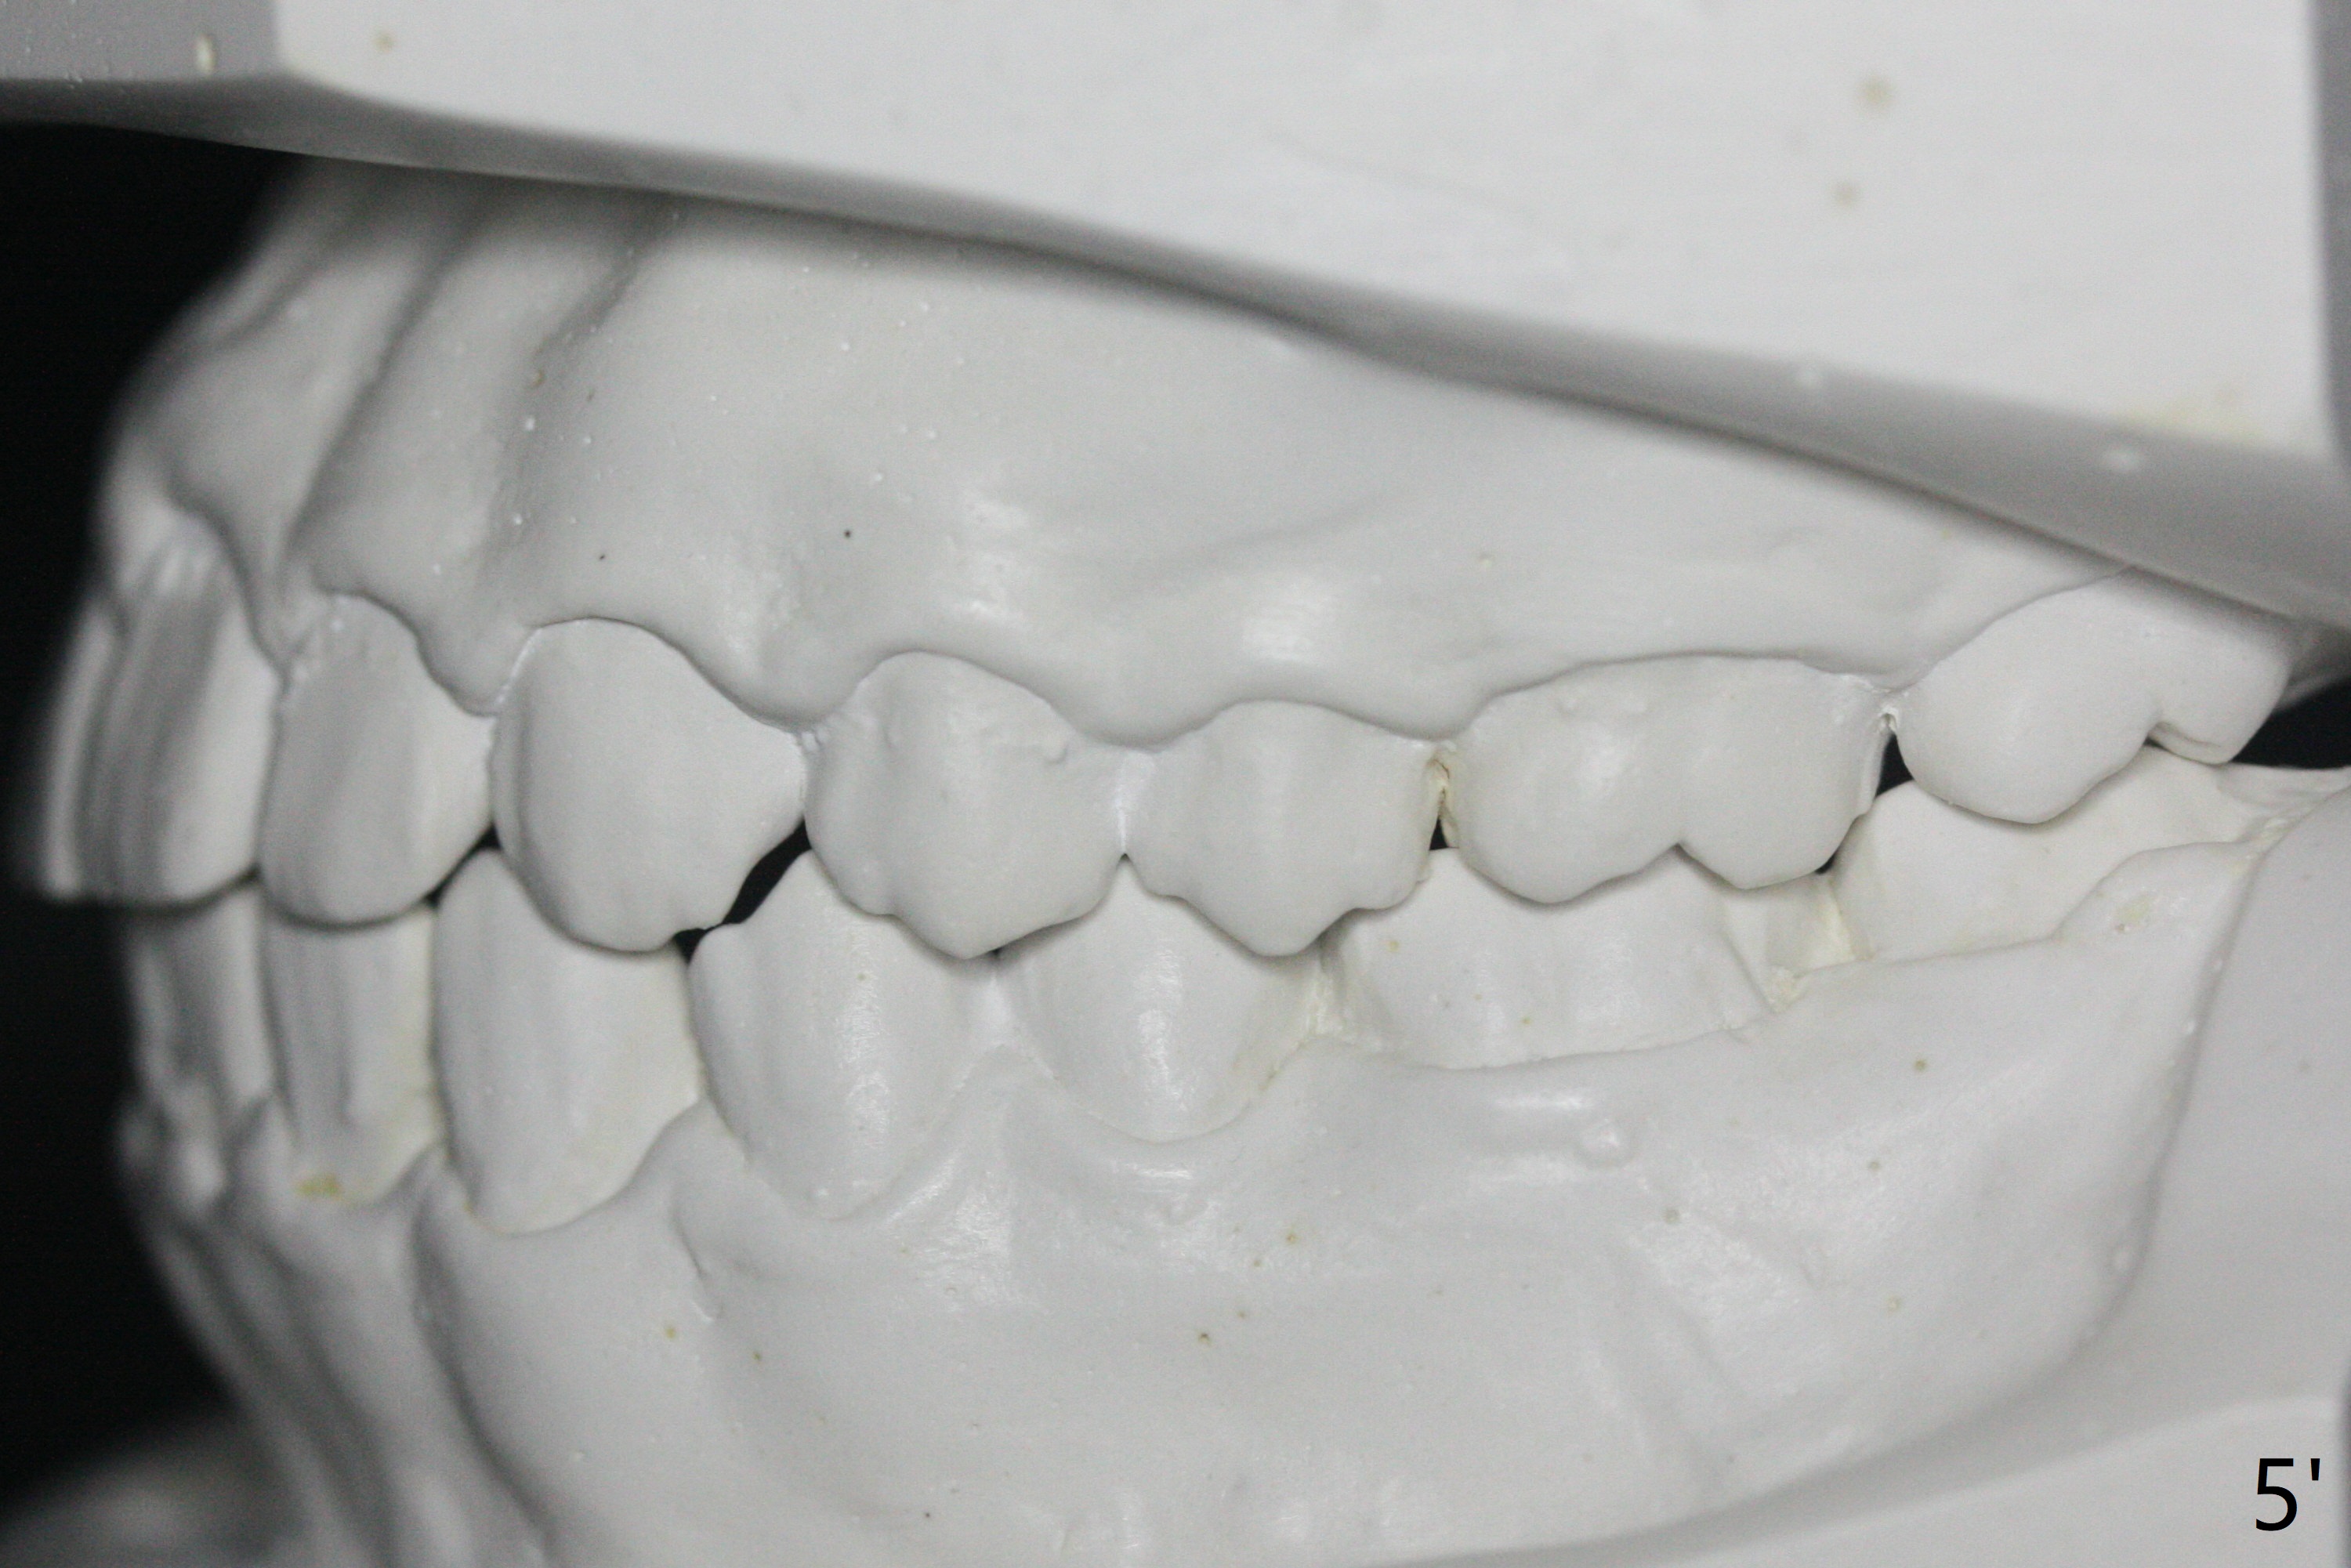

A 15-year-old man finishes orthodontic treatment for congenital missing lateral in 13 months. Molar Class I relationship remains the same (Fig.1,2,4,5). The upper diastemata mesial to 4s (Fig.4,7") close with correction of the upper midline deviation (Fig.2'-4'). The kid is unpleased with the elongated UR1 (Fig.2',3'). In fact it is a preexisting condition (Fig.2 arrow, 2"), but bracket placement at UR1 should have been overcorrected (incisal placement, Fig.3"). The intrusion should be done (Fig.4") before closure of the diastemata, since anchorage may be weakened when the separation between UR1 and 3 increases by using open coil spring. To prevent immediate relapse of the diastema between the upper central incisors, a fixed retainer is placed lingual before debracketing (Fig.6,6',6").